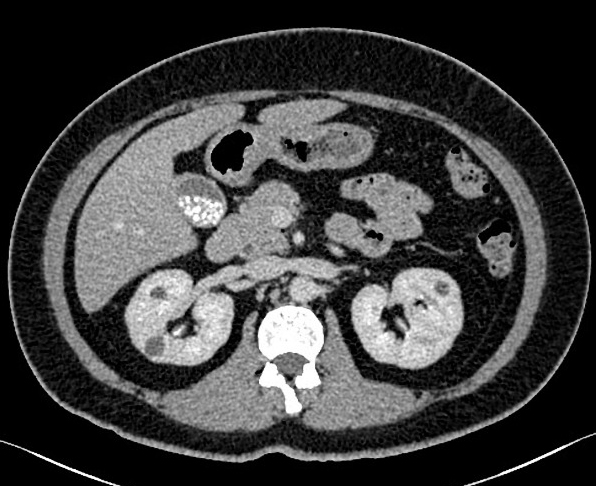

Image TDM :

Selon de la propiete des calculs vesiculaires ,

calcique ou cholesteolique ,les calculs vesiculaires se donne

de image hypodense ( cholesterolique ) ou hyperdense (

calcique ) que la bile . Quel que calcul biliaire peut done

de image a isodense avec la bile de la vesicule biliaire .

Image de epaissisememnt parietale et dilatation de voies

biliaire peut se en voyait

Calcul

vesiculaire de type pigmentaire en coupe

TDM axiale a non contrast . Forme arrondie a contour

calcique hyperdense et radiolucence a hypodense

centrale . La vesicule biliaire est pres isodense

avec le foie |

Image radiologique TDM en

coupe axiale de contrast intra veineuse . Calcul

pigmentaire de la vesicule biliaire , le foie en

contrast est hyperdense que la vesicule biliaire ,

paroie de la vesicule et canall cystique se en

voyant nette |